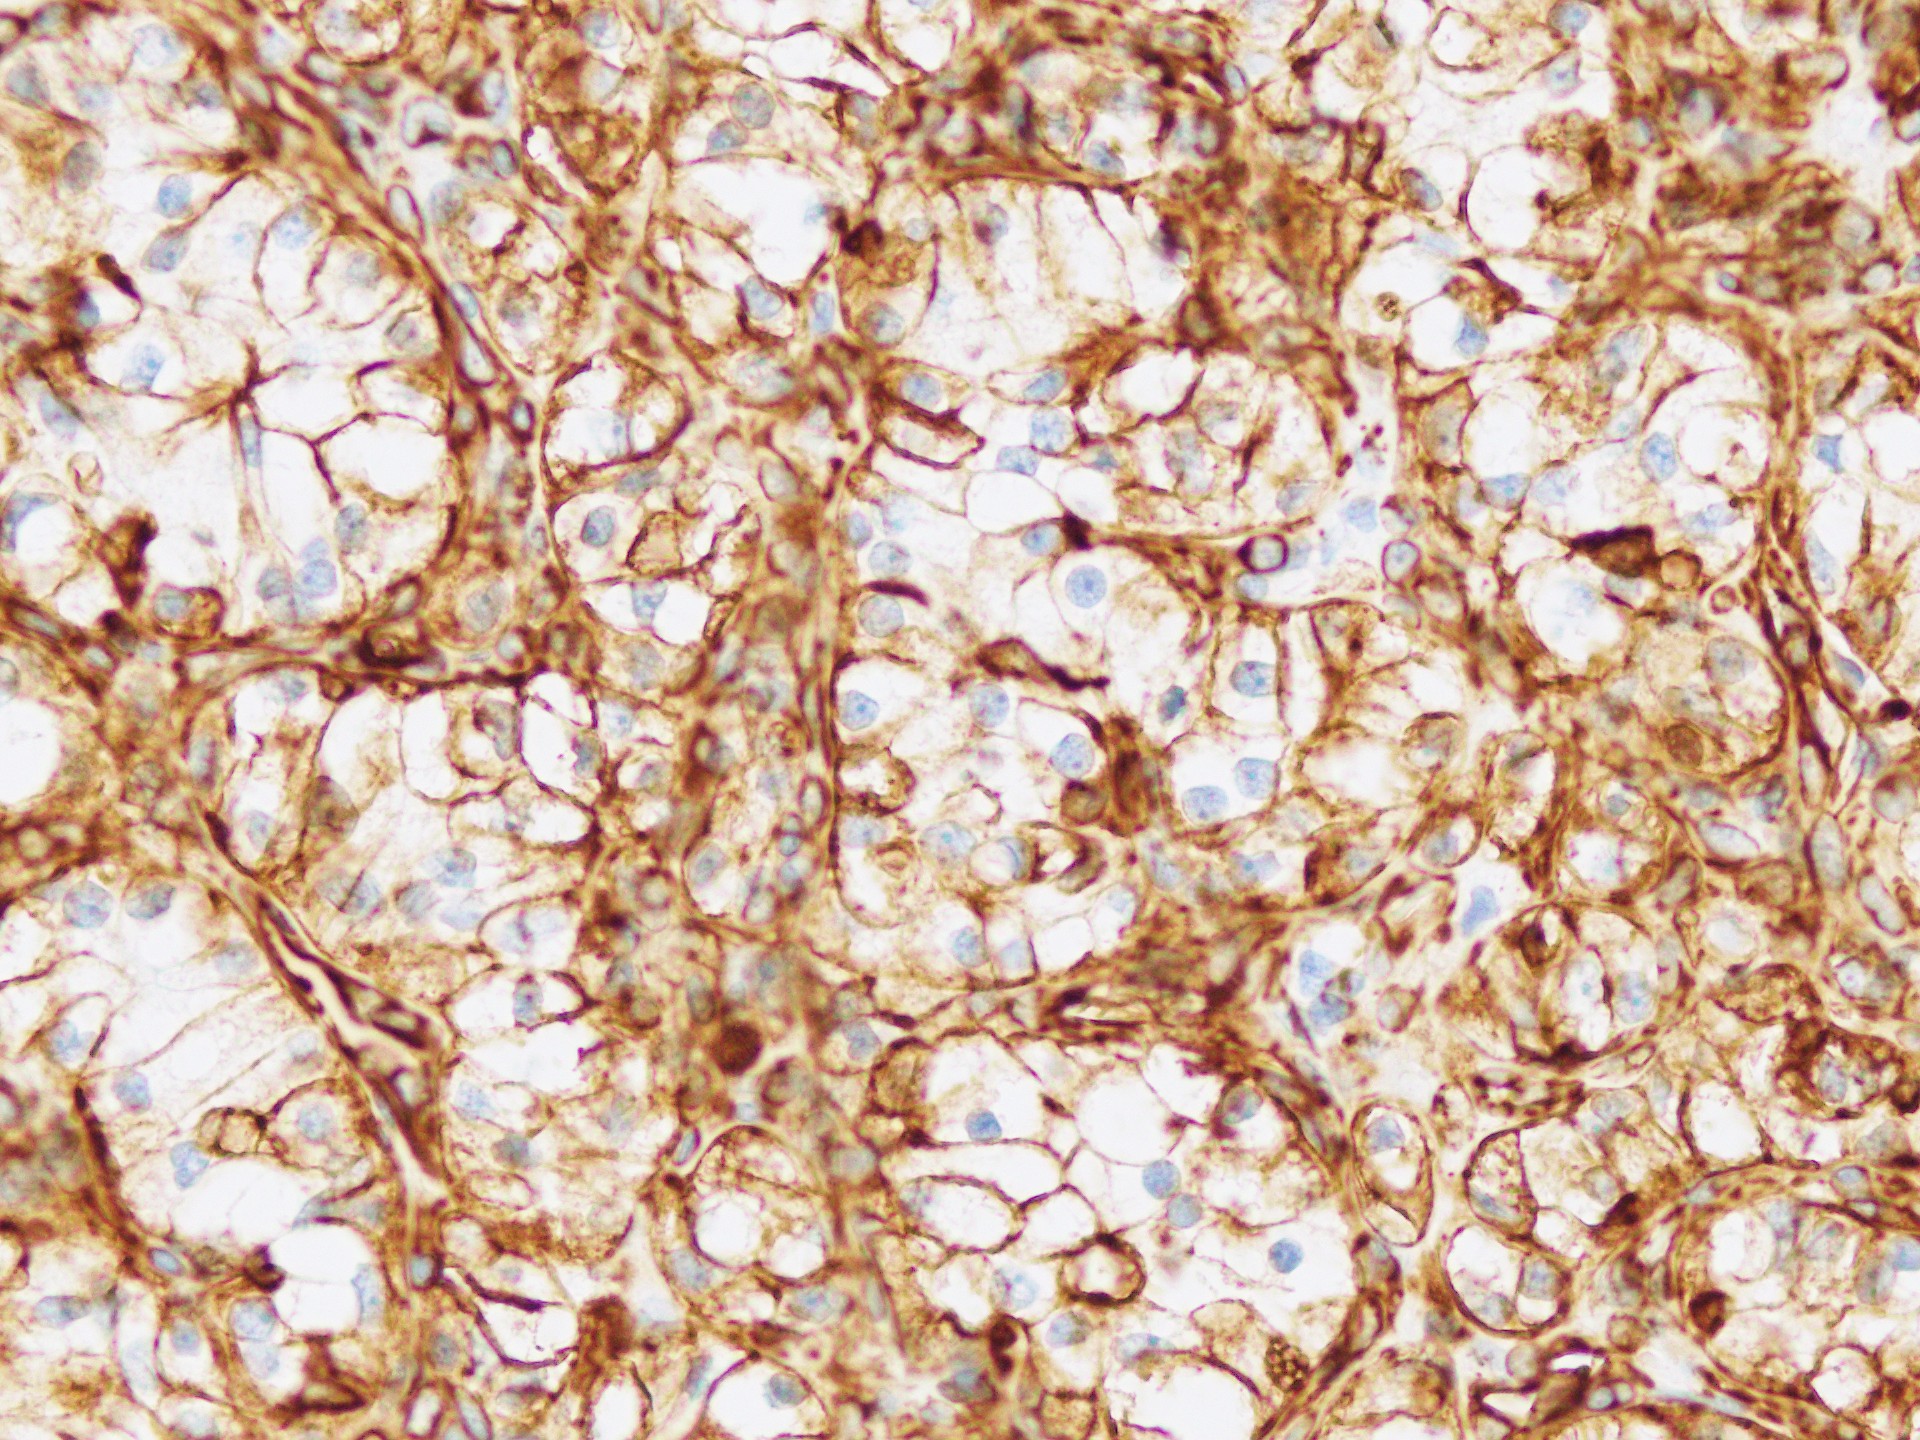

免疫組織化学染色ではCD10,Vimenntinが陽性で上記診断を指示する結果でした。

HE×4 HE×40 Vimenntin